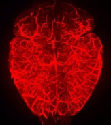

生物组织样品在单细胞分辨率尺度的结构信息是基础研究和临床病理诊断的关键基础。但是,长期以来,生物组织样品的表征与检测都是基于组织切片技术来实现。这种表征方法的最大缺点是难以获得完整组织3D的结构信息和空间关系,即“只见树木,不见森林”。 本技术基于最新的组织透明化技术,发展和实现了一整套组织样品快速表征与检测的技术方法,包括:快速组织透明化、快速组织样品免疫染色、3D组织成像和3D图像数据处理与展示。该技术的产业化将能推动传统的组织学与胚胎学的研究从2D时代进入3D时代,并逐步进入临床组织病理的检测领域,真正实现基于3D组织病理的精准医疗。

1. 与现有技术相比,可测量样品的深度提高3倍以上; 2. 与现有技术相比,样品标记的时间减少10倍以上,标记成本节省10倍以上